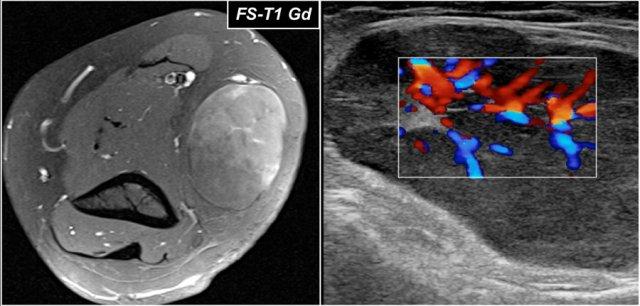

Đây là hình ảnh siêu âm của một nam giới 73 tuổi, xuất hiện đau đột ngột và cảm giác rách khi nâng một hộp đồ.

Có đau khi sấp và ngửa cẳng tay, ấn đau ở phía trước gần khớp khuỷu.

Không có bầm máu hay khối u sờ thấy được.

Trên hình ảnh mặt phẳng đứng dọc, gân bị dày lên, nhưng ở phần xa gân không còn hiển thị.

Đã thực hiện kiểm tra MRI.

Bây giờ hãy xem các hình ảnh MRI và cố gắng xác định xem gân có bị co rút không và liệu đó là rách một phần hay rách hoàn toàn…

Trên hình ảnh mặt phẳng đứng dọc, có vẻ như gân bị đứt hoàn toàn, nhưng hãy tiếp tục xem các hình ảnh tiếp theo.

Tear of distal biceps tendon

Có một vết rách hoàn toàn, vì nếu chúng ta theo dõi gân đến tận củ quay, chúng ta có thể thấy rằng gân không bám vào đó (mũi tên xanh lá).

Chỉ có dịch.

Lý do tại sao gân không bị co rút là vì cân cơ nhị đầu rộng – còn được gọi là lacertus fibrosus – vẫn còn nguyên vẹn (mũi tên đỏ).

Gân nhị đầu xa không chỉ bám vào lồi củ xương quay, mà còn thông qua lacertus fibrosus bám vào cân cơ của khối cơ gấp-sấp ở phía trong cẳng tay.

Gân xa của cơ nhị đầu được khoanh tròn ở hình ảnh phía trên bên trái.

Khi cân cơ cũng bị rách, thì gân sẽ co rút lại và bạn sẽ thấy một khối phồng rõ ràng ở cánh tay do cơ nhị đầu bị co lại.